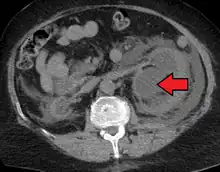

Massive hydronephrosis as marked by the arrow.- Renal ultrasonography of hydronephrosis[14]

- Urine jets[14]